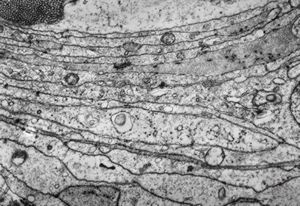

M,71y. | CADASIL accompanied with Alzheimer disease - brain vessel - arrows: granular osmiophilic material (GOM) between basement membranes

M,71y. | CADASIL accompanied with Alzheimer disease - brain vessel - arrow: granular osmiophilic material (GOM) in basement membrane